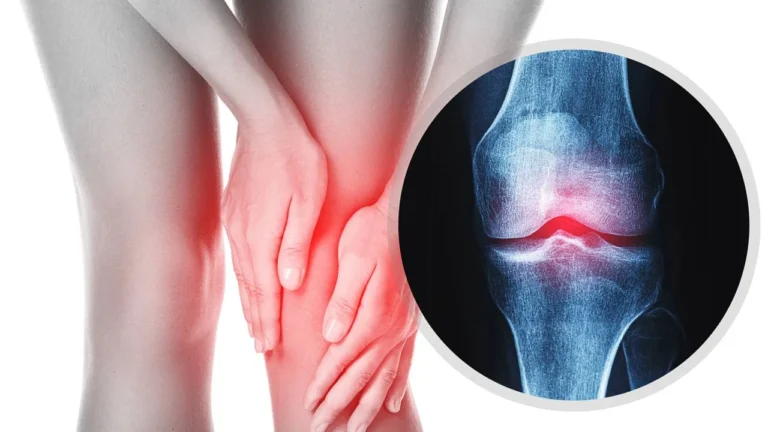

O Impacto da Atividade Física na Osteoartrite

Conviver com a osteoartrite leva muitas pessoas a evitarem a atividade física, temendo que o movimento possa intensificar a dor nas articulações. Entretanto, pesquisas recentes mostram que a prática regular de exercícios é fundamental para aliviar o desconforto e melhorar a mobilidade, especialmente em articulações que geralmente são mais afetadas, como joelhos, quadris e a coluna.

Um estilo de vida sedentário pode agravar os sintomas da osteoartrite. Músculos enfraquecidos não protegem adequadamente as articulações, e a cartilagem passa a receber menos nutrientes, o que potencializa a inflamação. Esse cenário cria um ciclo vicioso: menos movimento resulta em mais dor, e a dor, por sua vez, leva a uma redução ainda maior na atividade física.